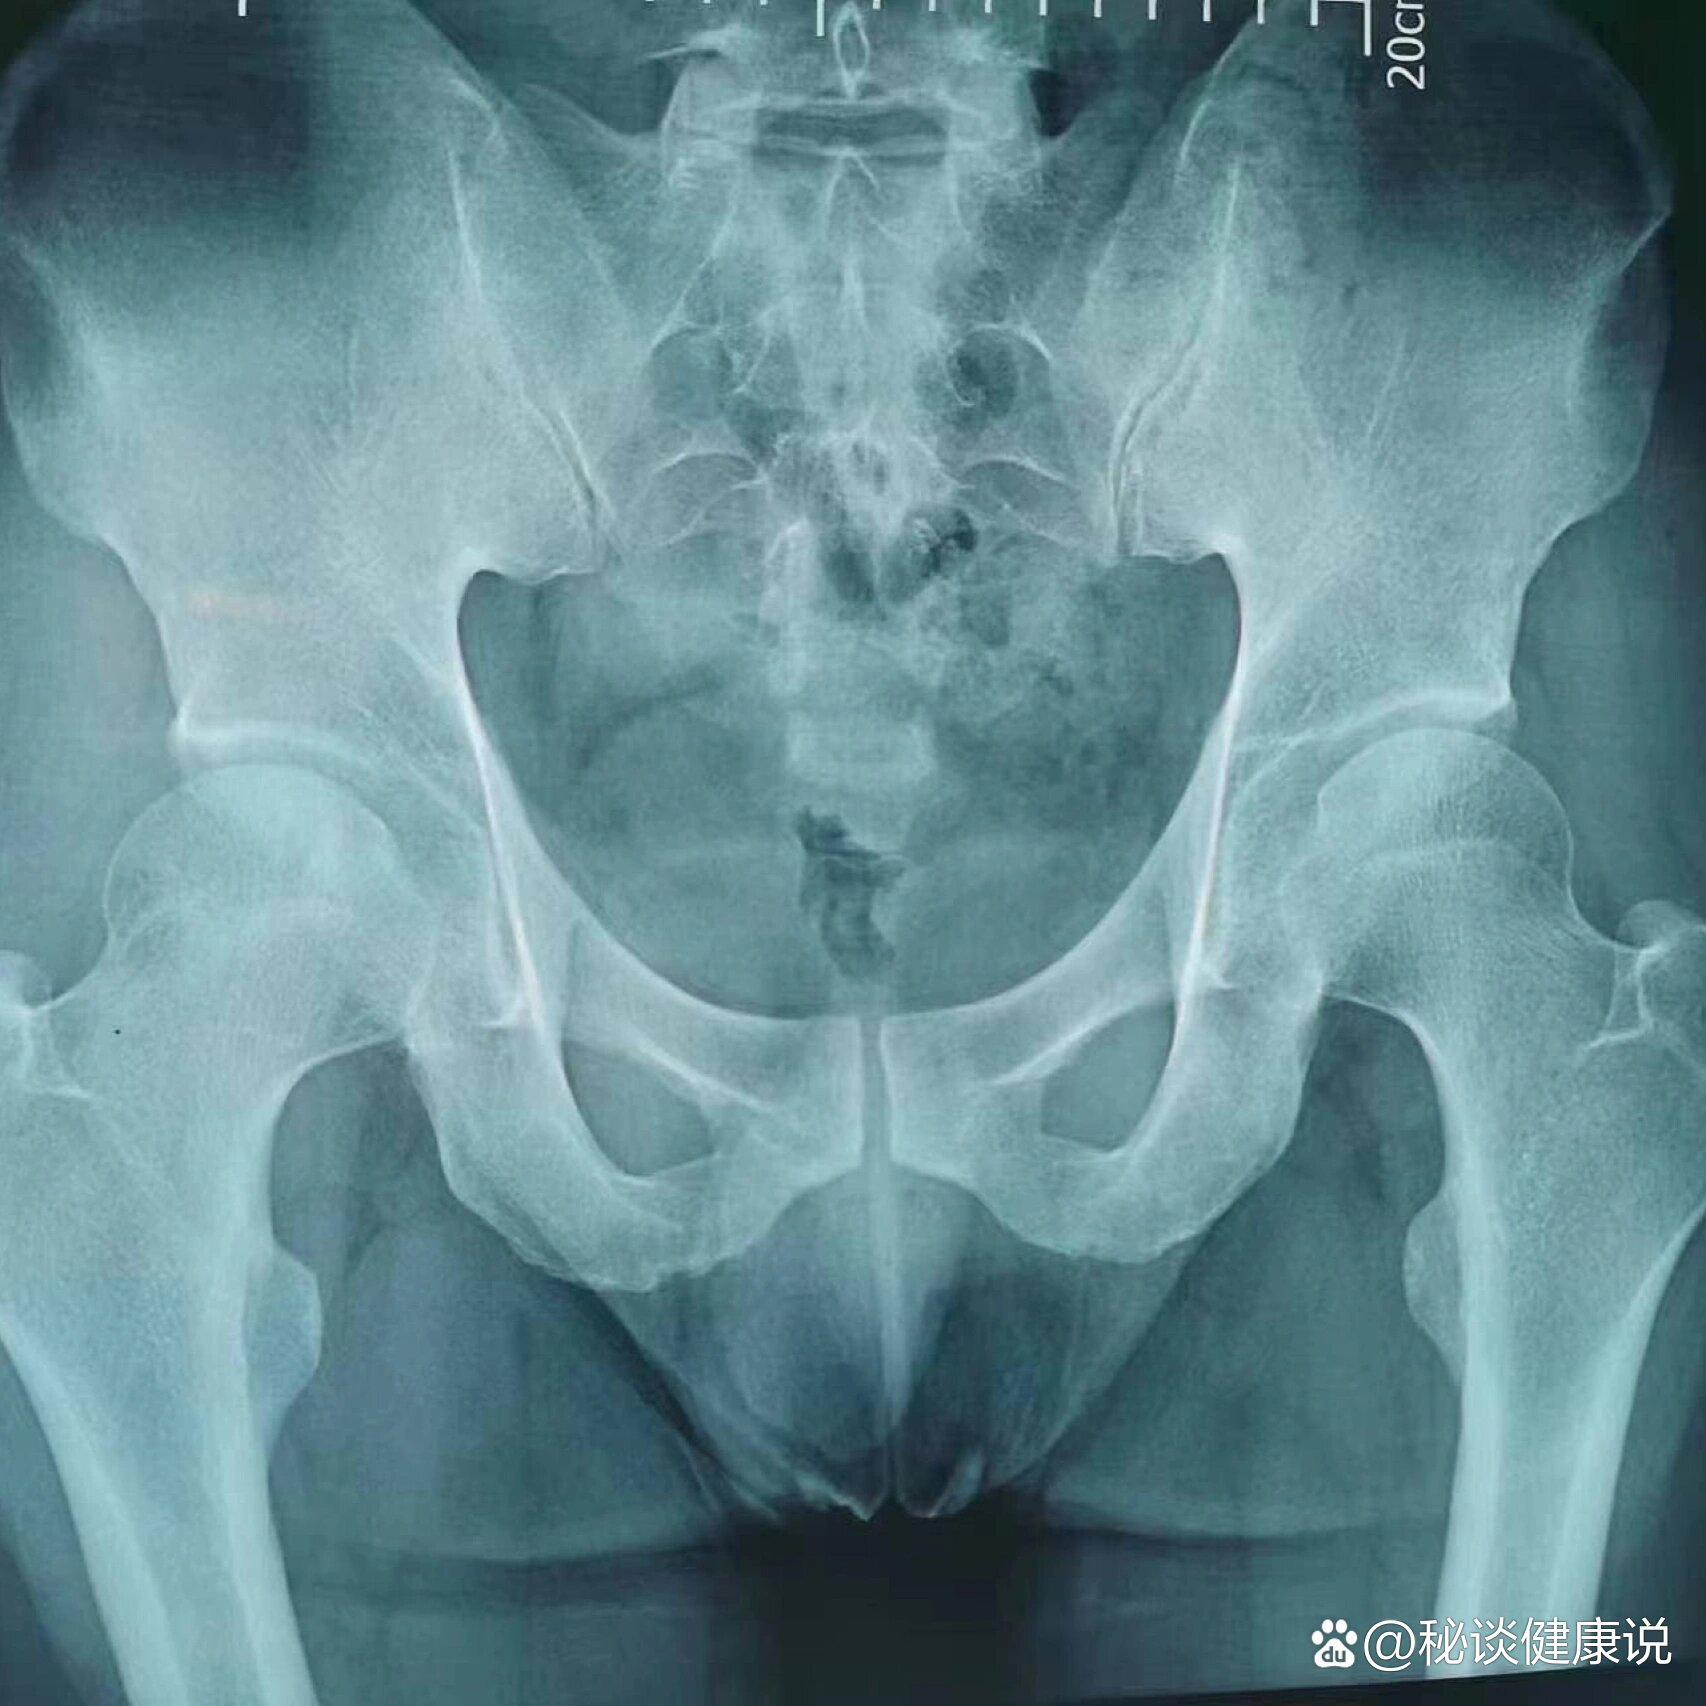

股骨头坏死X片

股骨头坏死